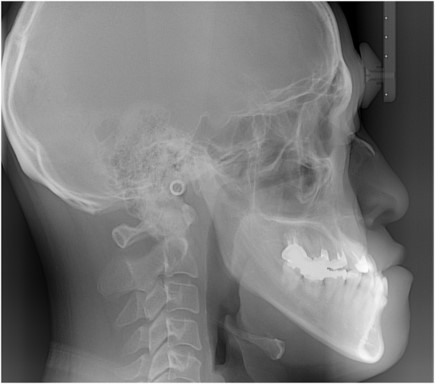

いなちゃんの顎のレントゲン写真はある?

稲田直樹さんほどの特徴的な顎となると、多くの人が骨格の構造に興味を持つのは自然なことです。実際に、レントゲン写真があるのか調べてみました。

残念ながら、稲田さん本人のレントゲン写真は公開されていません。

過去に他の芸人さんがアップしたレントゲン画像に対して「もしかしたら稲田さん?」というコメントがついたことがありましたが、それは完全に別人のものでした。

劇的ビフォーアフター#顎変形症 #手術 #レントゲン pic.twitter.com/Qf0v95ORDo

— もりた(森田悠介) (@bassyusuke) February 26, 2022

医学的な観点から見ると、特徴的な顎の構造はレントゲンで見れば一目瞭然のはずですが、プライバシーの観点からも、そのような医療情報が公開されることはないでしょう。